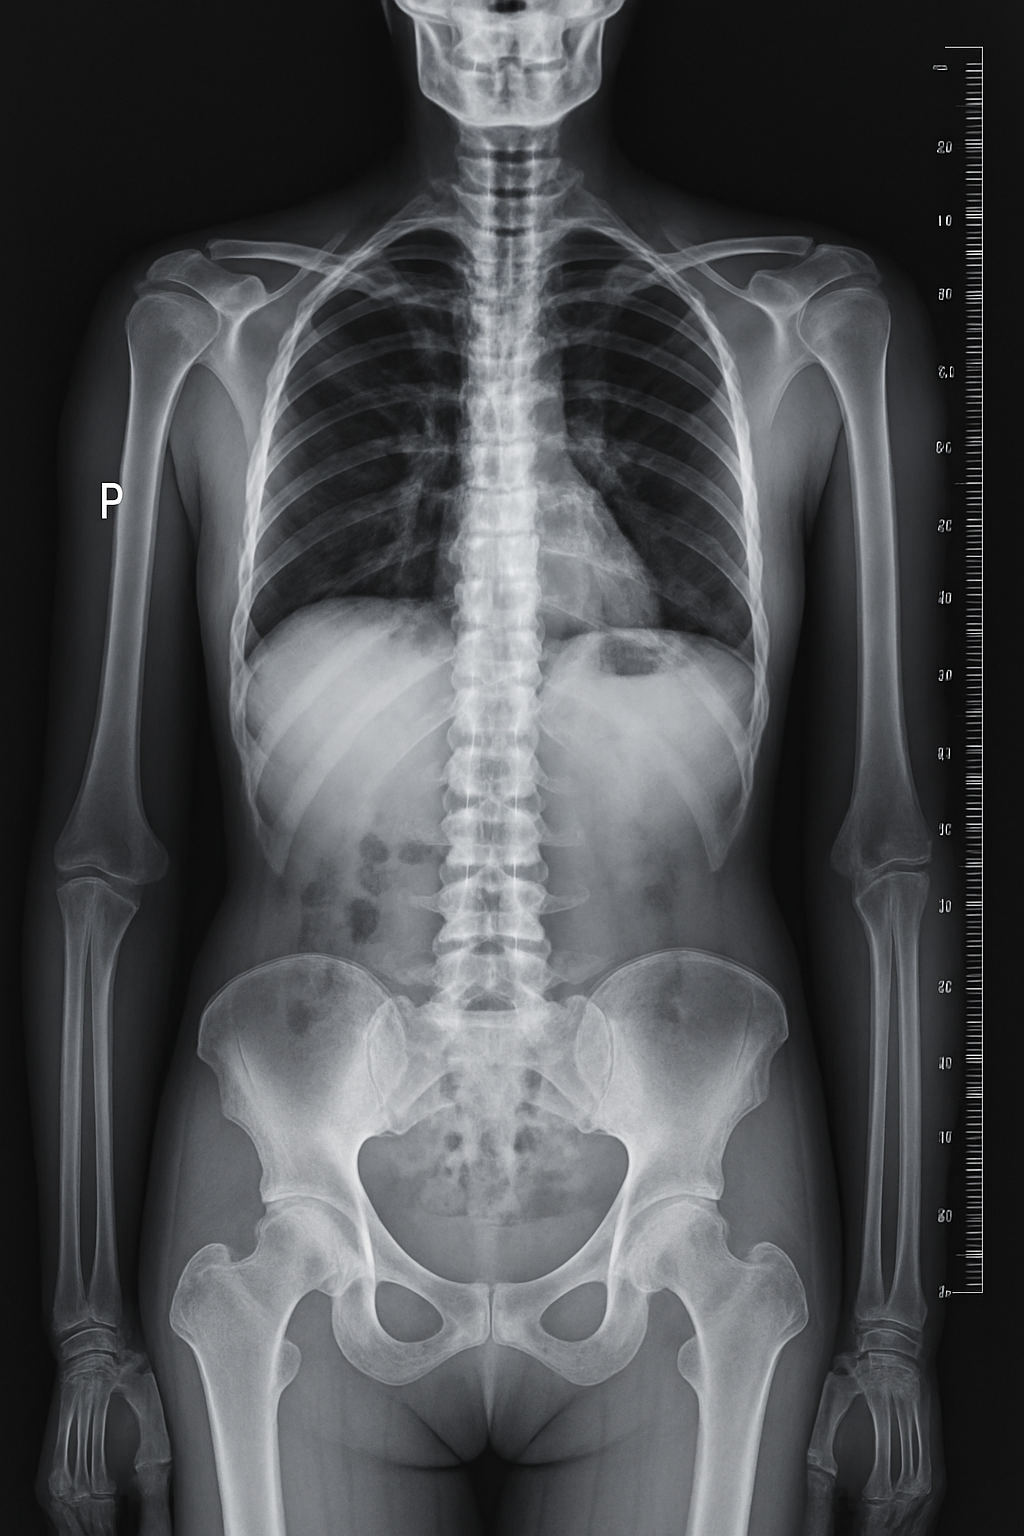

Nowoczesna pracownia RTG

Oferujemy szybką i precyzyjną diagnostykę obrazową w komfortowych warunkach. Nasza pracownia wyposażona jest w najnowszy system cyfrowy, gwarantujący najwyższą jakość przy minimalnej dawce promieniowania.